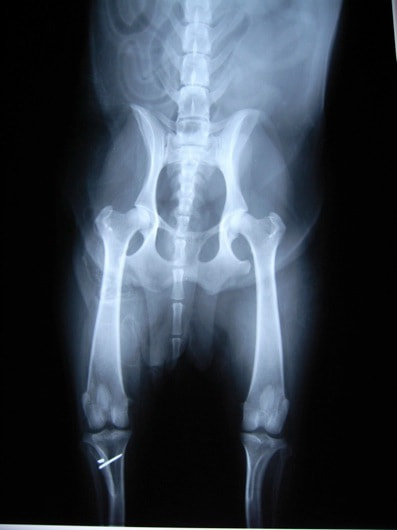

■ 症例24 キャバリア 7か月

左右膝蓋骨内方脱臼(左:グレードⅣ 右:グレードⅢ)

以前から左右後肢の跛行が認められ、整形外科学的検査・レントゲン検査により左右の膝蓋骨脱臼が認められた。症状が重度である左膝の膝蓋骨脱臼整復術を行った。外科手技は縫工筋及び内側広筋の解放、脛骨粗面の外側転位、滑車ブロック形造溝術、内外側関節方の縫縮を実施した。術後一か月時点で、左の膝蓋骨は安定しており経過は良好である。

本症例は成長期における重度の膝蓋骨脱臼であり、術後の再発の可能性もあるため、経過をしっかりと観察していく必要がある。また、今回手術を実施していない右膝に関しても経過を観察し、手術を検討していくこととする。